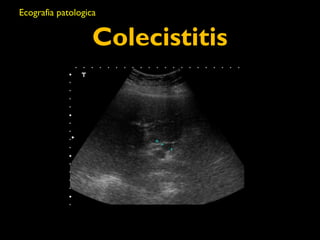

Colecistitis

• Hallazgos ecográficos en la Coleciistitis:

• Colelitiasis

• Engrosamiento de la pared vesicular

• Liquido perivesicular

• Signo ecográfico de Murphy

• Pared anterior grosor: <4mm

• Promedio de 9 mm en la colecistitis aguda